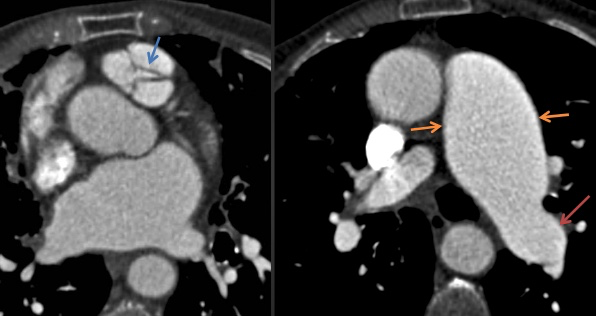

Insuffisance Aortique

- En lien avec une dilatation de la racine aortique (sur Atherosclerose ou Marfan) ou avec une calcification sévère des feuillets

- Une autre cause plus rare: Bicuspide Aortique, Endocardite, RAA

- Dilatation ET Hypertrophie du VG